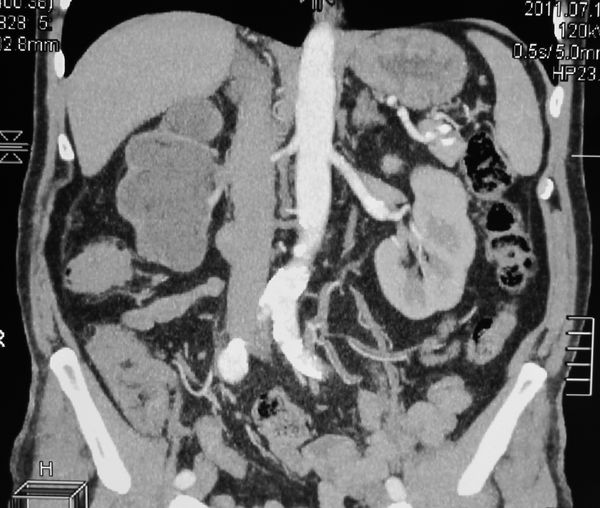

Гидронефротическая трансформация правой почки. Паренхима источнена. ее практически нет.